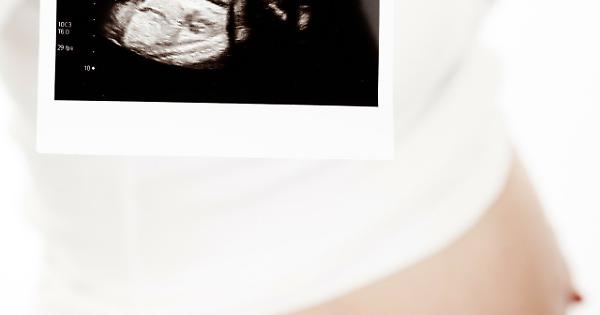

“Il mio paziente nascerà più in là”

Il follow-up ostetrico del futuro è già presente in Poliambulatorio Delta Medica

Ecografia

Sempre più spesso, i servizi erogati per la tutela del benessere e della salute della Donna e del Bambino rappresentano un indicatore di qualità dell’intera offerta sanitaria erogata alla comunità. Nell’ottica di tale “concezione moderna di salute”, la medicina materno-fetale non può non ricoprire un ruolo prioritario, essendo l’unico momento della vita di una donna in cui “è possibile definire il benessere del paziente presente (mamma) e del paziente futuro (feto)”. Per molteplici aspetti socio-economici, la maternità ha subito negli ultimi anni notevoli cambiamenti, in primis fra tutti l’essersi spostata come evento nella “medio-tarda” età fertile. Tale tendenza, che non potrà che continuare, induce nella coppia la pianificazione di un numero sempre inferiore di figli, spesso ricorrendo a tecniche di procreazione medicalmente assistita (e quando necessario anche con utilizzo di gameti eterologhi), aumenta potenzialmente i rischi materni e fetali (gravidanza a rischio), ma al contempo incrementa esponenzialmente il desiderio/necessità di predizione di benessere. Ecco che diventa “normale” la richiesta della coppia del “massimo” in termini di aspettativa di salute, di predizione del rischio e di diagnosi rapide, veloci, esaustive ed accurate. Il Poliambulatorio Affidea Delta Medica in collaborazione con il Dr. Gizzo Salvatore - Specialista in Ginecologica ed Ostetricia – offe già da alcuni anni la possibilità alla donna incinta di soddisfare, con minimo tempo di attesa e costi contenuti, il desiderio di predizione di benessere suo del suo futuro nascituro. Ecco che, oltre alla routinaria visita ostetrica, è possibile nella stessa occasione effettuare l’ecografia ostetrica ad hoc per qualsiasi epoca gestazionale. L’ecografia ostetrica, oltra al battito cardiaco fetale e alla diagnosi di presentazione permette di valutare il rischio di patologie cromosomiche già nel primo trimestre di gravidanza (ecografia genetica del primo trimestre). L’ecografia del secondo trimestre, meglio conosciuta come ecografia morfologica, è il massimo concentrato delle potenzialità dello studio ecografico: questa è l’epoca gestazionale in cui si ha il miglior rapporto tra le dimensioni del feto stesso e la risoluzione dell’apparecchio, al fine di eseguire un’analisi morfostrutturale. Si possono investigare estensivamente parametri della crescita e del benessere fetale, implementando lo studio con la visualizzazione e valutazione della vascolarizzazione fetale ed uterina. Nelle successive settimane di gravidanza è possibile monitorare il benessere fetale e di realizzare uno studio particolareggiato della struttura, valutarne l’accrescimento, con la possibilità attraverso complesse formule matematiche di determinare una stima del peso e della lunghezza fetale al momento stesso e con buona approssimazione al parto. Le pazienti che si rivolgono al Poliambulatorio Affidea Delta Medica potranno usufruire inoltre di test di screening genetici non invasivi di 1° livello (Ultrascreen o meglio conosciuto come Bi-Test) nonché del sempre più diffuso e richiesto “Test del Dna Fetale circolante [cfDNA]”. I test basati sul cfDNA, in quanto analisi del DNA, sono test genetici a tutti gli effetti, potendo eseguire uno screening cromosomico ad elevata performance (altra sensibilità ed alta specificità) sia per le cromosomopatie più frequenti quali trisomia 21 (sindrome di Down), trisomia 18 (sindrome di Edwards), trisomia 13 (sindrome di Patau), aneuploidie (monosomie e trisomie) dei cromosomi sessuali (e definizione del sesso fetale) fino all’estensione dell’indagine alla ricerca delle microdelezioni più frequenti del genoma umano o all’intero genoma stesso (cariotipo digitale). Per tale motivo il Poliambulatorio Affidea Delta Medica offre alle pazienti interessate una consulenza totalmente gratuita con il Dr. Salvatore Gizzo sia pre-test al fine di informare e coadiuvare la coppia nella scelta dell’indagine a loro più pertinente sia post test al fine di elucidarne i risultati ed offrire, in caso di test positivo, un continuum assistenziale con eventuali altre indagini necessarie. Il NIPT dove essere collegato e preceduto da un accurato controllo ecografico dopo l’XI settimana, effettuato da operatori accreditati ed esperti in indagine ecografica del primo trimestre. E’ infatti possibile eseguire con il Dr. Gizzo Salvatore sia alcuni giorni prima sia nello stesso momento del prelievo ematico per test cfDNA l’ecografia del primo trimestre. Grazie alla moderna ed avanzata tecnologia presente e all’expertise degli operatori, presso il Poliambulatorio Delta Medica è possibile estendere l’indagine ecografica bidimensionale con ricostruzioni tridimensionali e anche quadridimensionali (3D/4D), ovvero con una modellazione solida in real-time. E’ ormai possibile spiare nel più recondito dei misteri: una vita portata in grembo. Inoltre è possibile vedere il proprio bambino muoversi, toccare il proprio corpo, così come osservare le espressioni del suo corpo. E’ possibile entrare in diretto contatto visivo con lui fino ad indovinarne le somiglianze. Si tratta di un’ecografia particolarmente sofisticata. I vantaggi, oltre che di tipo emotivo, sono enormi dal punto di vista diagnostico tant’è che nella nostra sede l’indagine 3D/4D viene eseguito su richiesta della gestante e in tutti i casi in cui il medico lo ritenga utile. La possibilità anche per le pazienti affette da gravidanza a rischio di poter essere seguite presso il Poliambulatorio Delta Medica in maniera completa e multidisciplinare completa quello che è considerato “un moderno approccio” alla tutela della salute della mamma e del futuro nascituro. Il ginecologo che si occupa di medicina materno fetale ha quindi l’insostituibile ruolo di presentare “step by step” ai futuri genitori il loro figlio, così da aumentarne la consapevolezza durante la gravidanza. I routinari controlli sono un momento in cui in cui i genitori trovano rassicurazioni e risposte ai molti dubbi e domande. Per una mamma, poter “vedere il bambino che porta in grembo, sapere che è sano e che la gravidanza sta procedendo bene” significa essere rassicurata sulla propria salute e su quella del proprio figlio. Tutto ciò ha un effetto positivo generale che influisce sulla percezione ed il buon andamento della gravidanza stessa. Dott. Salvatore Gizzo Specialista in Ginecologia ed Ostetricia Affidea - Uni-x Poliambulatorio P.za Giuseppe Dossetti 1, 35028 Piove di Sacco (PD) - T 049 9708688 www.deltamedica.affidea.it